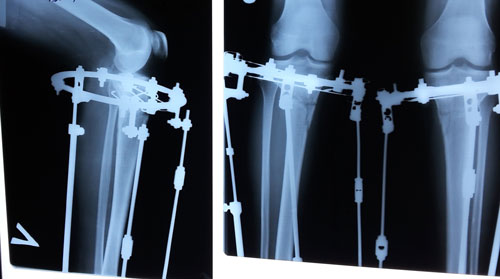

Рентген в 62 дня.

Сращение идёт отлично для этого срока и возраста пациентки.